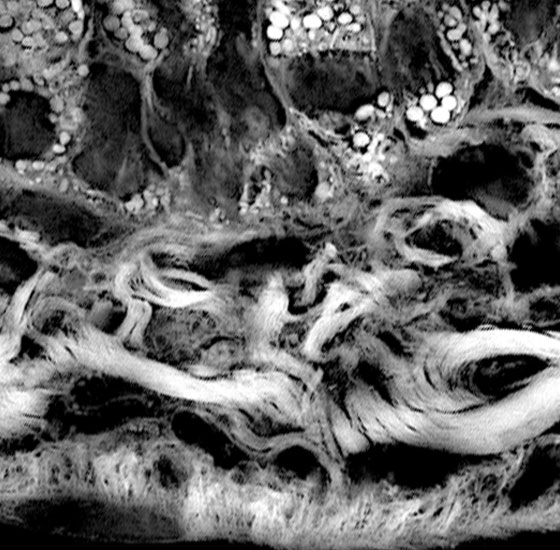

本研究領域では、炎症が収束する際の生体反応を、組織レジリエンス、炎症記憶として研究を進める一方で、慢性炎症時の病態形成機構について、「炎症性組織レジリエンス」、「病的炎症記憶」および「組織障害エントロピー」として捉え、複数の生体システムの連関の観点から研究を推進することにより新たな炎症収束学の創成を目指します。